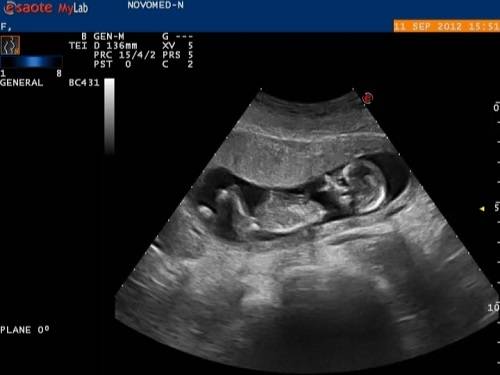

Признаки патологии обнаруживаются еще во время УЗИ, проводимого в первом или втором триместре. Точность описания и подтверждение диагноза, тем не менее, невозможно сделать до рождения ребенка.

Иногда считают, что обнаруженные во время УЗИ признаки заячьей губы являются основанием для искусственного прерывания беременности. Вопрос этот решается медицинской комиссией только при наличии других пороков развития, которые угрожают жизни ребенка.

Ультразвуковое исследование на четырнадцатой-шестнадцатой неделе беременности способно предварительно диагностировать образовавшуюся волчью пасть у плода, но точно установить факт патологии и оценить объем поражения неба в полной мере можно только после появления малыша на свет.